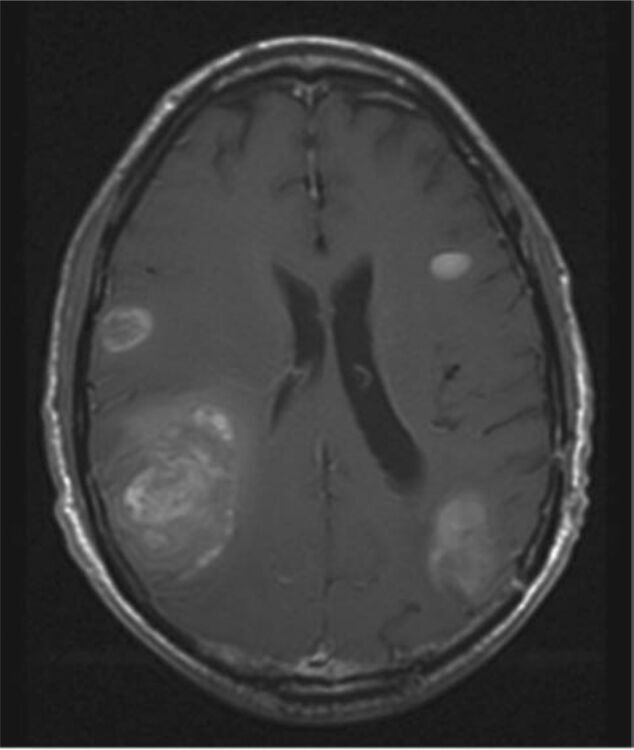

Brain Metastasis Tumor Board

Join us every Thursday at 8 AM for a unique and informative Zoom event where medical experts gather to conduct a Brain Metastasis Tumor Board. During this virtual gathering, doctors will meticulously review complex patient cases, sharing their insights and knowledge on the latest advancements in brain metastasis treatment. This interactive event is a valuable opportunity to witness the collaboration of top multi-disciplinary medical professionals as they discuss challenging cases and explore innovative solutions. To participate, registration for the event is required. Don't miss out on this weekly insight into the world of brain metastasis treatment and research! Hosted by: Kathryn Beal, M.D. Associate Professor of Radiation Oncology Director of the Center for Brain Metastasis and Survivorship of the Department of Radiation Oncology and Meyer Cancer Center Elcin Zan, M.D. Assistant Professor of Radiology Divisions of Molecular Imaging and Therapeutics & Neuroradiology Rohan Ramakrishna, M.D. Chief of Neurological Surgery, Brooklyn Methodist Hospital Associate Professor Co-Director, Rhodes Center for Glioblastoma Director, Brain Metastases Program